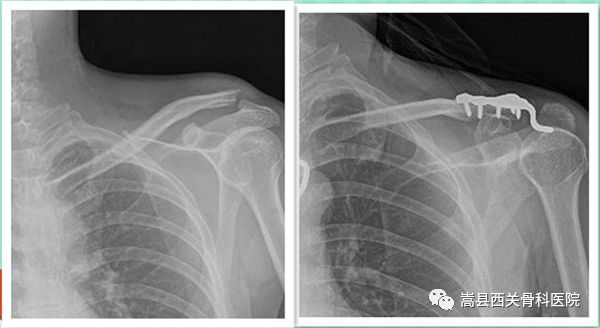

锁骨远端骨折伴有喙锁韧带损伤,稳定性较差,临床上常推荐带钩锁骨钢板,至于喙锁韧带是否修复,仍存在较大争议。

我院上肢创伤科部分患者术前术后对比图